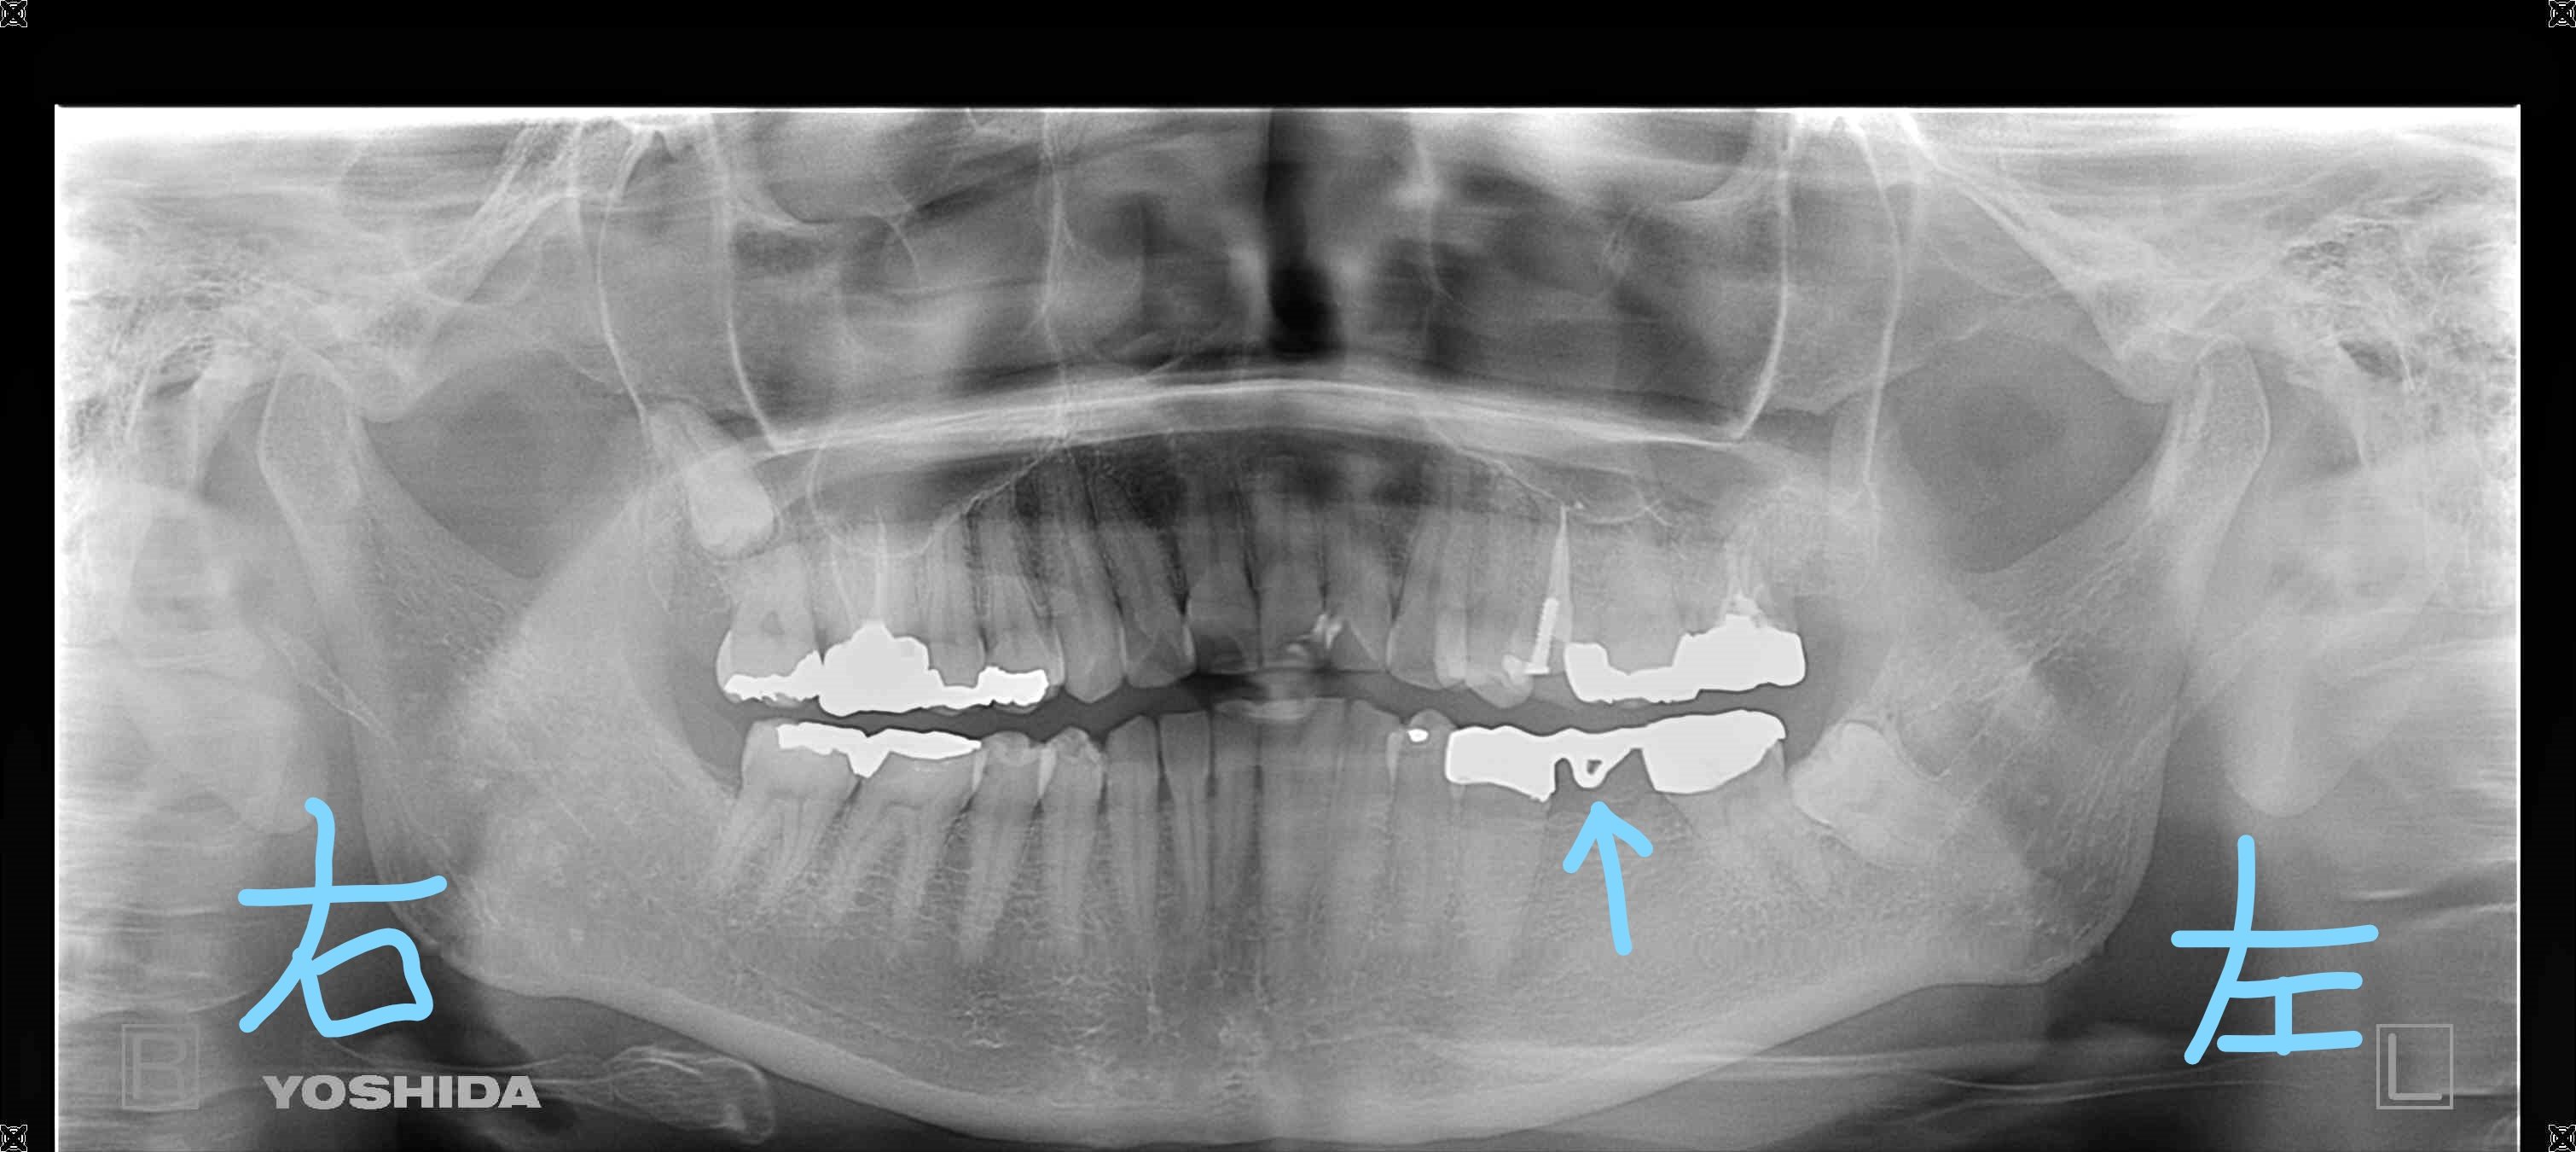

初診時のレントゲン写真(左下の図)では、左下奥歯にブリッジ(被せ物)が設置されていましたが、ぐらつきがあり脱落の恐れがある状態でした(図中水色矢印部)。このブリッジは、歯のない部位を補うため、両隣の歯を大きく削って被せて固定するタイプの人工歯です。